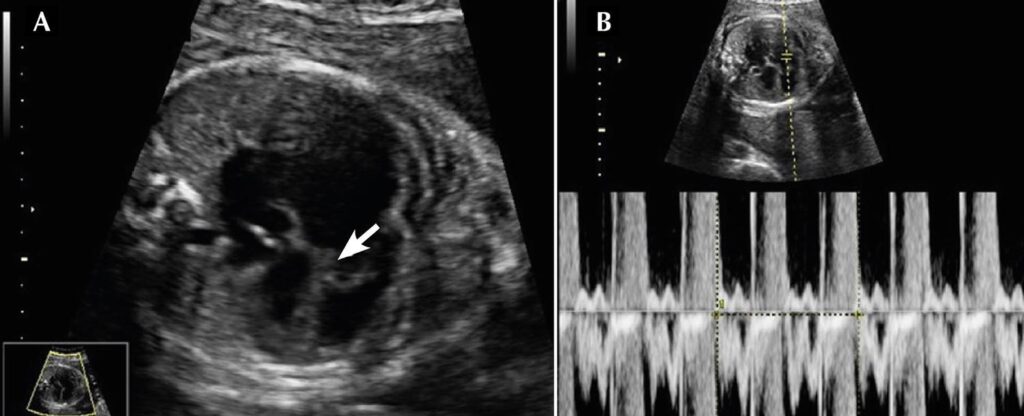

O ecocardiograma fetal com 25 semanas demonstrou cardiomegalia, acolamento do folheto septal da valva tricúspide no septo interventricular e insuficiência tricúspide importante, compatível com anomalia de Ebstein (). Foi detectado derrame pericárdico discreto, tendo sido estimado o escore cardiovascular de Hutha 6. A artéria pulmonar mostrava bom calibre (escore-Z de 1,9) (), sem fluxo anterógrado, apenas com fluxo retrógrado oriundo do canal arterial, caracterizando o shunt circular. Com 29 semanas de gestação, foi observado feto em hidropisia, fluxo na artéria umbilical diástole zero e escore de Hutha 4 (). O óbito fetal ocorreu com 30 semanas de gestação.